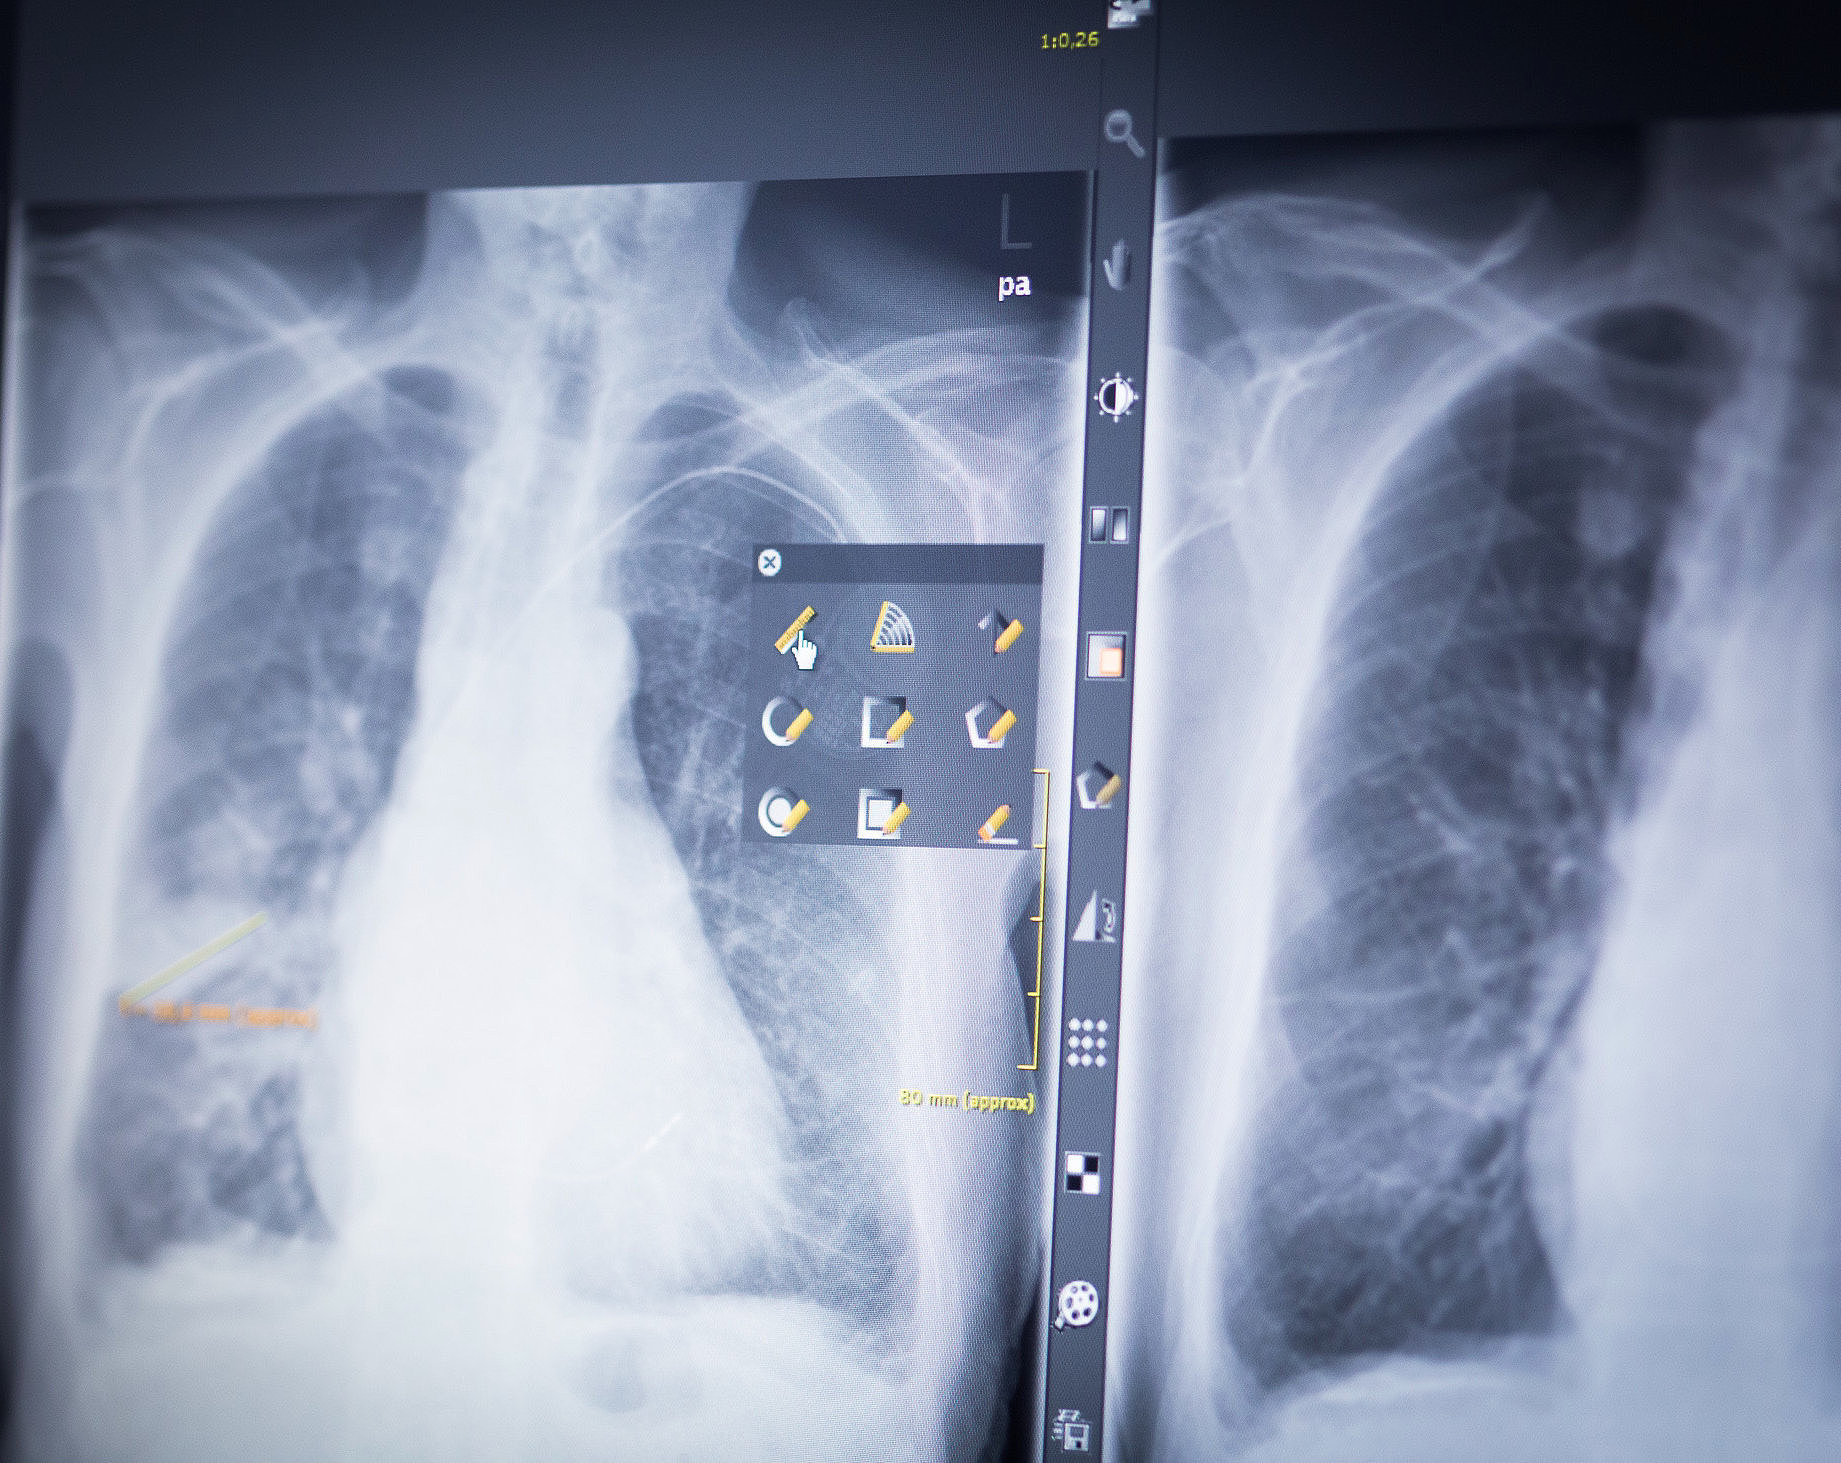

Wir sind mit der Radiologischen Praxis am St. Joseph Stift (www.radiologie-in-bremen.de) und mit der Nuklearmedizinischen Praxis am St. Joseph Stift

(http://www.nuklearmedizin-bremen.de) vernetzt. Im Bedarfsfall können wir auf die dort durchgeführten Untersuchungen digital zugreifen. Hierüber werden unnötige Doppeluntersuchungen vermieden. Die Befunde der von uns veranlassten Untersuchungen können sofort nach Fertigstellung besprochen werden.